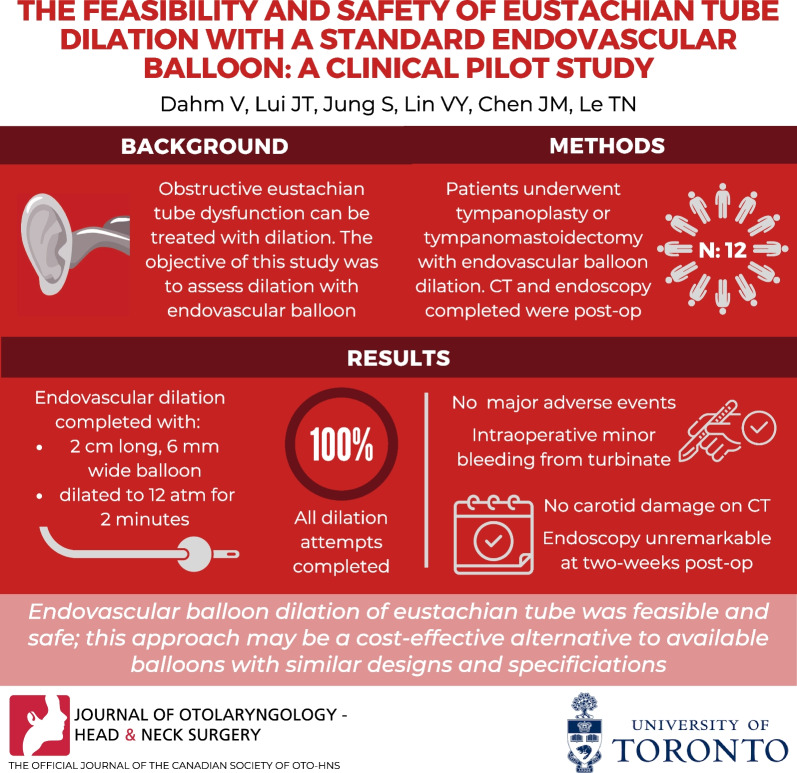

Fig. 1.

Endovascular balloon dilation system. A Endovascular balloon and pressure gauge. B Suction tips used for eustachian tube dilation. From left to right—suction tip with a 45° angled tip, suction tip with a 70° angled tip, “s” shaped malleable suction tip. C Balloon length marking along the distal end of endovascular balloon catheter. The EVB catheter was marked at its distal end (beyond the suction tip) to gauge the balloon length distance at which the entire balloon would be inserted into the eustachian tube

To guide the EVB to the opening of the ET, a curved metal sinus suction catheter was used (Fig. 1B). The balloon was inserted through the lumen of the suction catheter. Three different suction catheters were used. Two suction catheters were both 147 mm in length with an external diameter of 4 mm at the tip (37–14,239 Von Eicken Sinus Cannula Suction, Curved Short, Integra, Princeton, New Jersey, U.S.A.) The curved tip of said suction has an angle of about 70° (Fig. 1B); one of the suctions was altered to a 45° (Fig. 1B) angle by the manufacturer. The third suction used during the study was a malleable suction cannula (Fig. 1B), “S” shaped, 110 mm long and with a 3 mm diameter (MicroFrance®, Integra, Princeton, New Jersey, U.S.A.).

First the nasal cavity and the nasopharynx were inspected and the eustachian tube orifice identified. Once the tip of the catheter was manipulated to the ET opening, the balloon was introduced into its proximal lumen until the tip was visible at the distal end of the catheter. The EVB was inserted into the ET by slowly advancing it along the suction catheter using Seldinger technique. The suction catheter guide was then pulled back slightly to visualize the introduced balloon. The EVB was never advanced against pressure or resistance. Once the proximal silver marker of the 2 cm balloon was visible, it was not introduced further. The EVB was dilated with a pressure gauge to 12 atm. The dilated balloon was left in place for 2 min, deflated and retracted. Steps of BDET are depicted in Fig. 2. As an additional safety precaution, before inserting EVB into the ET orifice the balloon length was marked at the distal end of the suction catheter, see Fig. 1C, to avoid over-insertion of the device.